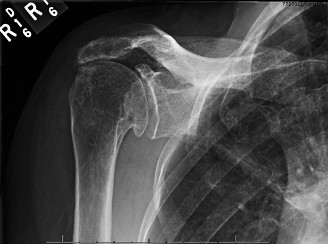

It should be noted that reverse total shoulder arthroplasty is also the procedure of choice in patients with cuff-tear arthropathy (aka rotator cuff arthropathy). Characteristics of cuff-tear arthropathy include superior migration of the humerus due to a massive rotator cuff tear, glenohumeral joint destruction, subchondral osteoporosis, and humeral head collapse (see Fig. 2–17). A reverse total shoulder

Figure 2–17_X-rays of a patient showing evidence of cuff tear arthropathy. The humerus is migrated superiorly, the glenohumeral joint is destroyed, there is subchondral osteoporosis, and the humeral head is collapsed. (From Ecklund KJ, Lee TQ, Tibone J, Gupta R. Rotator cuff tear arthropathy. _J Am Acad Orthop Surg. 2007;15(6):340–349.)